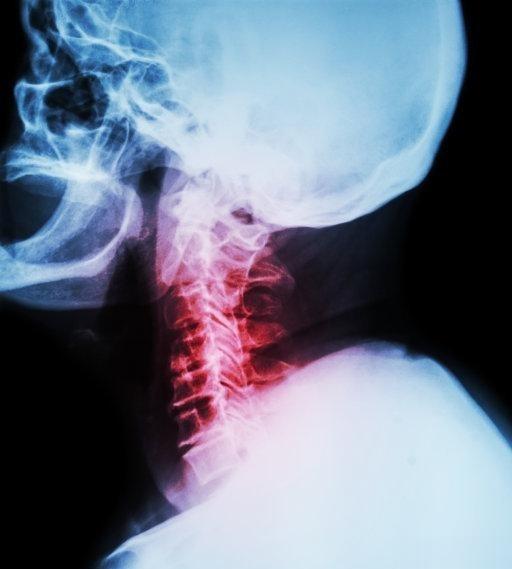

颈椎病是怎么引起的 1.颈椎的退行性变 颈椎退行性改变是颈椎病发病的主要原因

2023-06-21 09:04

老人在日常如何避免得颈椎病 1、注意颈部保暖。 可以用厚的长围巾对脖子进行保

老人家颈椎痛该怎么办 一、预防:颈椎病的产生 ①天气渐凉,颈部受风着凉会诱发

拯救“电脑脖” 基本姿势:每次做各项训练动作前,先自然站立,双目平视,双脚略